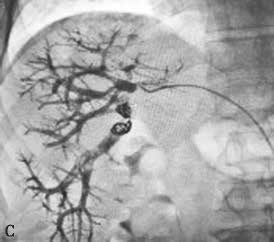

图2-5-1 采用不同栓塞材料实施PVE

B、b.氰基丙烯酸正丁酯栓塞门静脉右支和Ⅳ段支;

C、c.微钢圈联合氰基丙烯酸正丁酯栓塞门静脉右支。

PVE术后需警惕的并发症包括肝穿刺点出血、胆漏。此外,需警惕术后钢圈等栓塞材料移位导致栓塞对侧门静脉分支或主干栓塞(图2-5-2)。

PVE术后应常规监测门静脉血供,了解选择性门静脉栓塞支血管是否再通,是否发生其他门静脉分支血栓等情况,必要时可选用合适的栓塞材料或无水乙醇进行靶血管的再次栓塞。